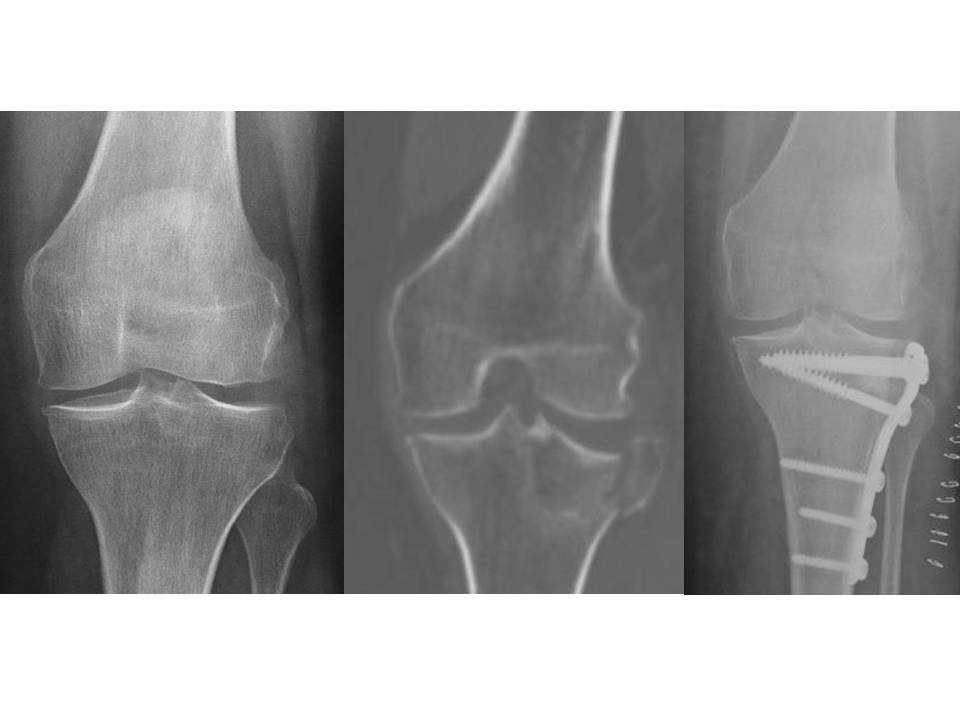

Hamburg, Deutschland) implantiert wurden. Für den Zuschnitt der Femurkondyle und des Tibiaplateaus wurde in der Gruppe mit dem PMI-System das System VisionaireTM (Smith&Nephew, Hamburg, Deutschland) genutzt. Im Zeitraum zwischen Januar 2008 und Dezember 2015 wurden im Hause 15 Patienten mit einer posttraumatischen Kniegelenksarthrose endoprothetisch versorgt. Hiervon waren zwei Patienten prä- und postoperativ auswertbar. Eine 63-jährige Patientin mit posttraumatischer Arthrose nach Tibiakopffraktur (Abb. 1) wurde mittels PMI-System versorgt (Abb. 2). Ein weiterer Patient (72 Jahre alt) wurde mit herkömmlicher Implantation versorgt (Abb. 3). Die Daten der Outcomes wurden mit hauseigenen Daten von 87 Patienten mit herkömmlicher Implantation und 84 Patienten mit PMI-gestützter Implantation verglichen. Das Durchschnittsalter der Patienten lag bei 71 respektive 66 Jahren. Das funktionelle Outcome wurde anhand des Oxford Knee Score und des Bewegungsumfanges beurteilt. Das radiologische Ergebnis wurde über die Veränderung der Knieachse sowie durch Bestimmung des medialen proximalen Tibia- und des distalen lateralen Femurwinkels (MPTA bzw. LDFA) in der Ganzbeinstandaufnahme sowie in der Messung des Slope in der seitlichen Aufnahme des Kniegelenks beurteilt. Es erfolgte die deskriptive Statistik mit Ermittlung von Maximum, Minimum, Mittelwert und Standardabweichung. Die Signifikanzprüfung erfolgte mittels Mann-Whitney-U-Test, wobei ein p-Wert von < 0,05 als signifikant angesehen wurde. Die statistische Auswertung aller Parameter erfolgte mit SPSS (Version 21.0).

Bei der Patientin mit posttraumatischer Gonarthrose, die mittels PMI versorgt wurde betrug der MPTA 89° und der mLDFA ebenfalls 89°. Der Slope lag bei 3°. Die mechanische Lastachse kreuzte das Tibiaplateau 2 mm medial des Fujisawapunktes. Die vorbestehende Valgusgonarthrose konnte somit gut korrigiert werden. Den radiologischen Verlauf zeigen die Abbildungen 1 und 2.